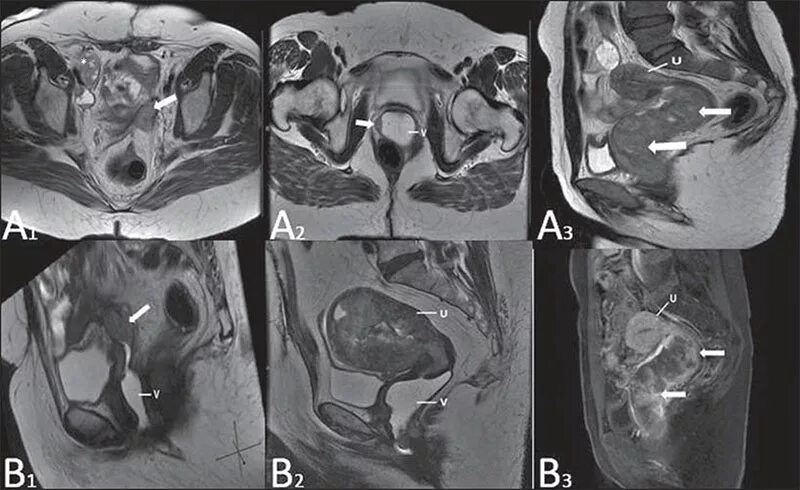

Мрт обп с контрастированием